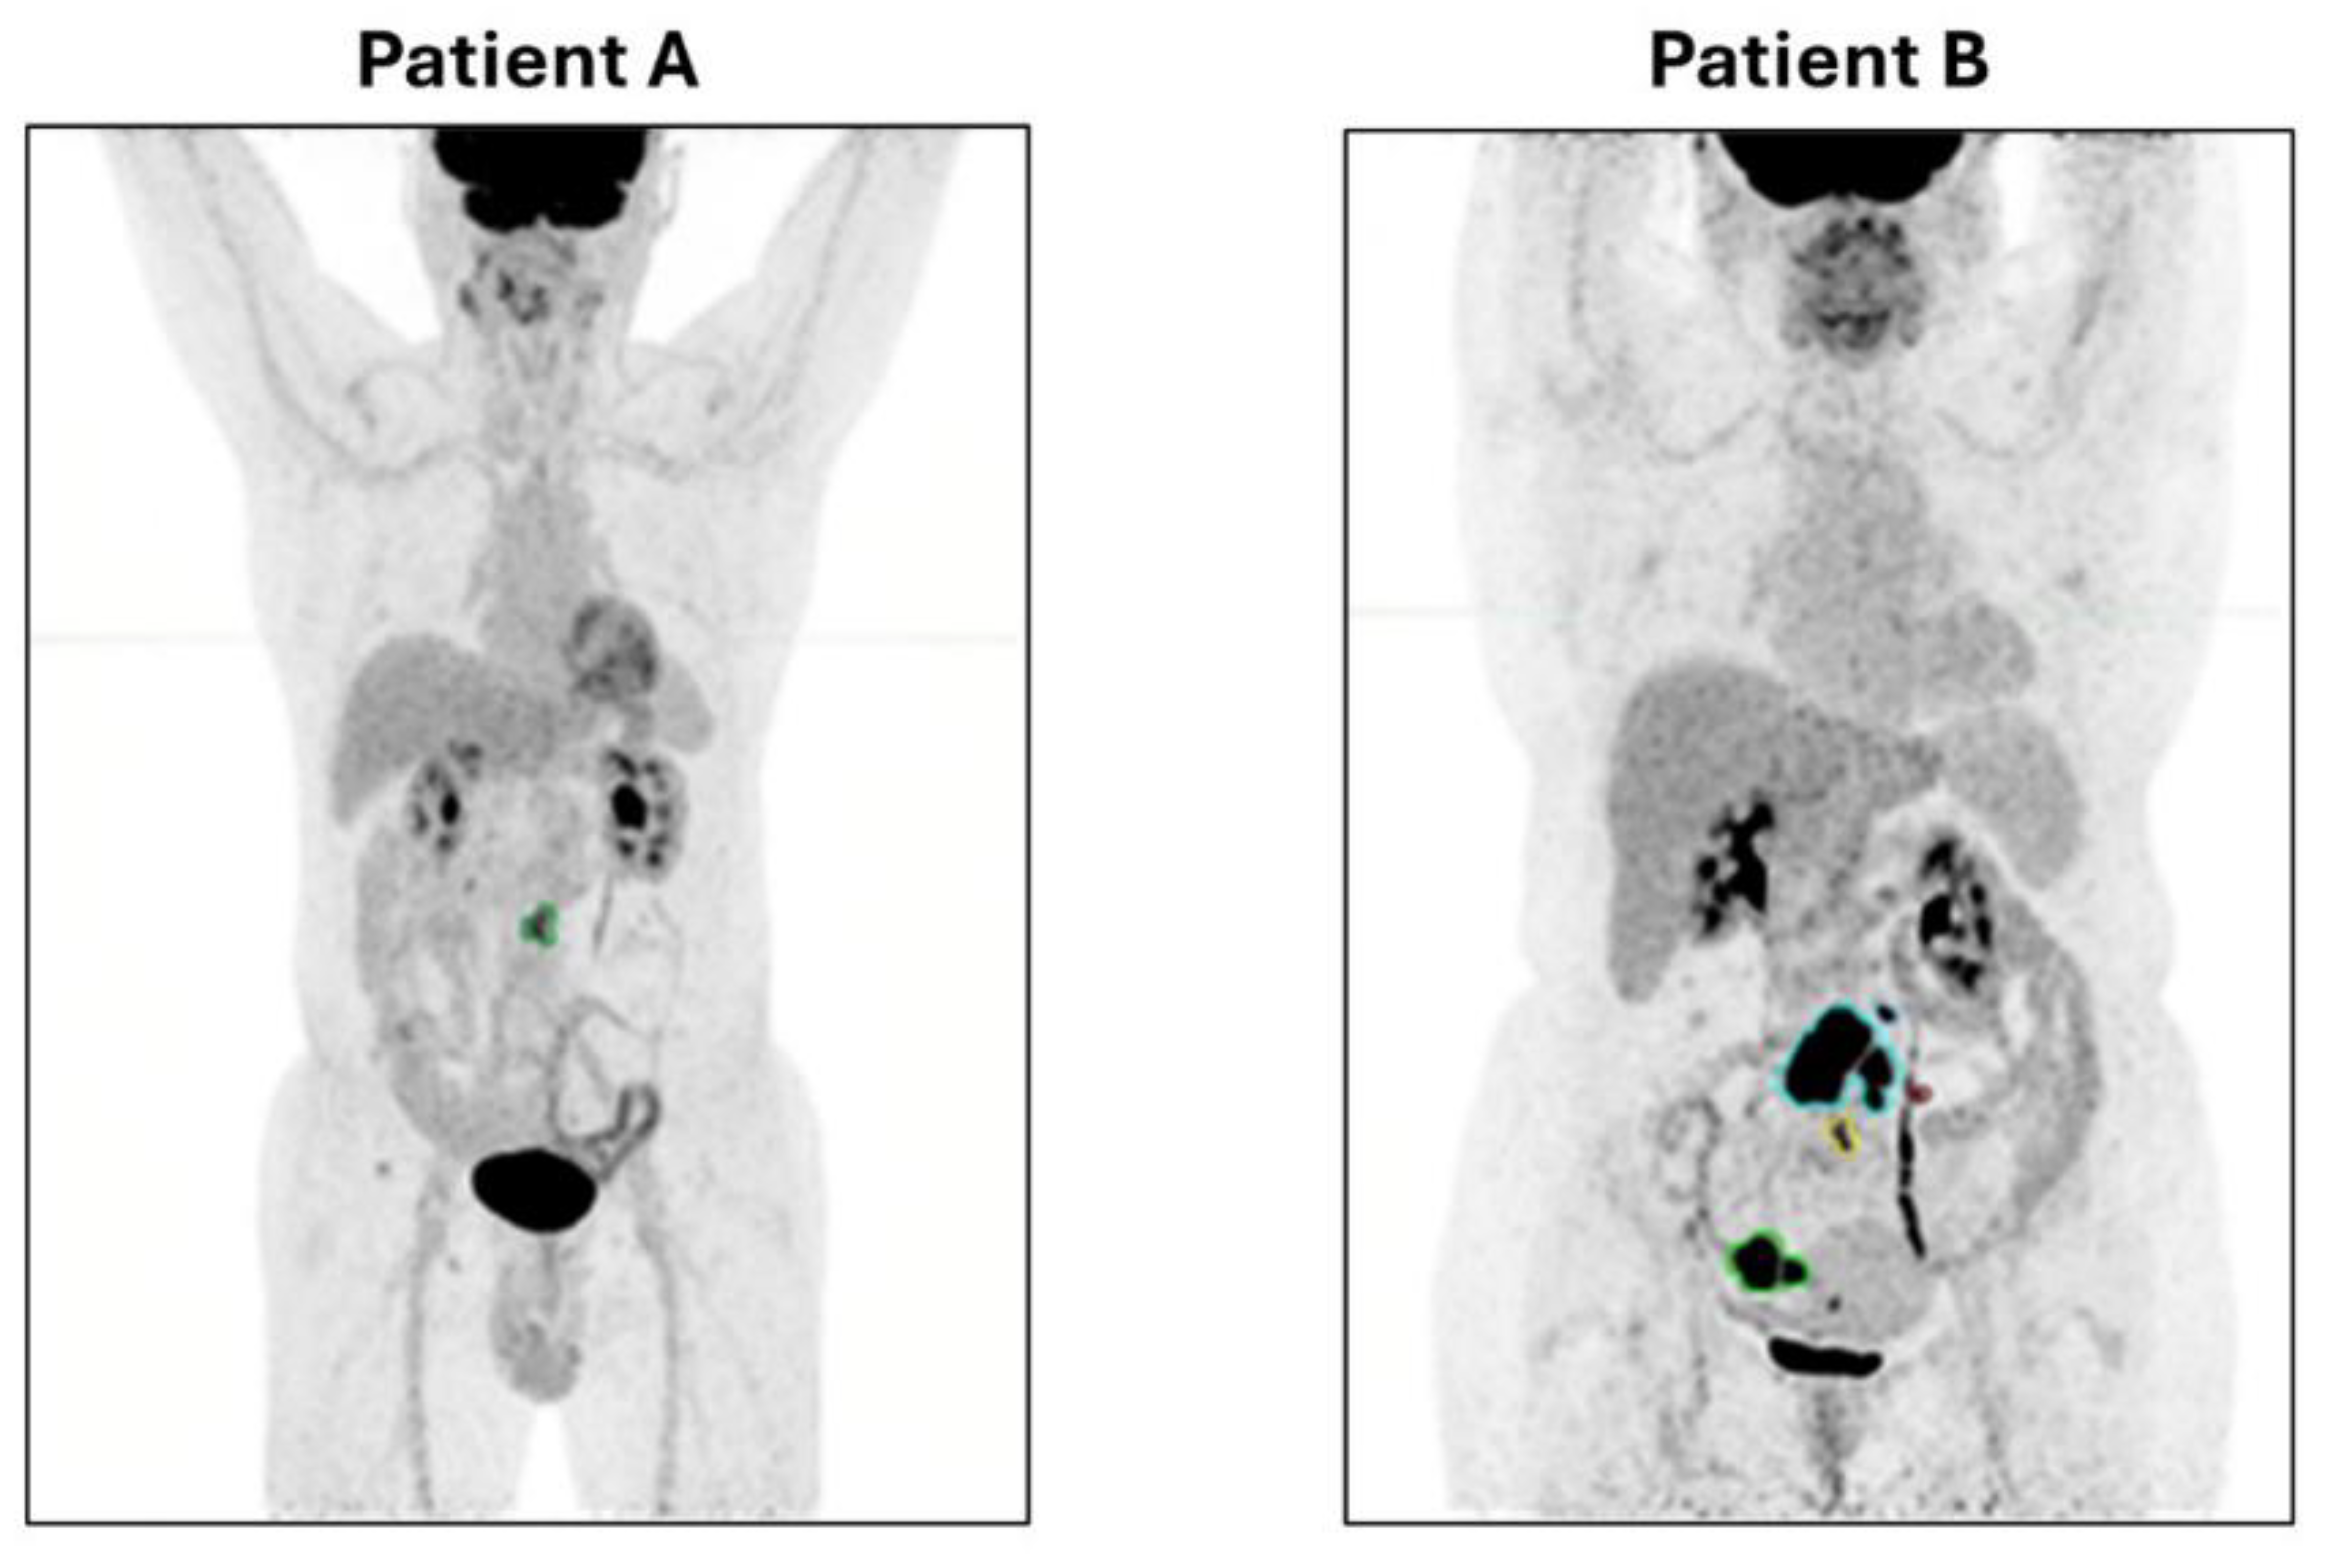

2.3. Image Segmentation

3.1. Contoured Lesions and PET Measurement Reproducibility